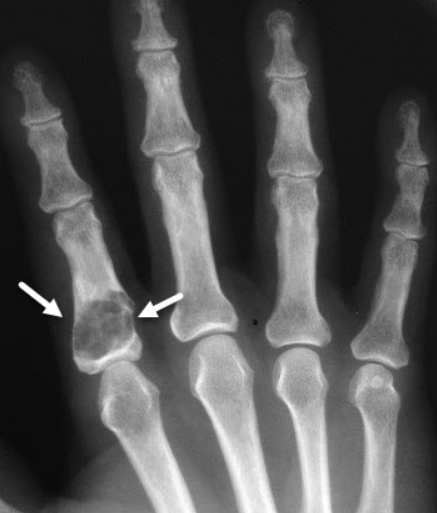

종양이 커지면 통증이나 부종이 나타날 수 있고, 뼈가 약해지면서 가벼운 충격에도 병적 골절이 쉽게 발생할 수 있습니다.

손가락 뼈가 부풀거나 변형되며, 드물게 신경을 눌러 감각마비가 올 수 있습니다.

주로 X-ray(단순 방사선 검사)로 진단하며, 필요에 따라 CT, MRI 등 추가 영상 검사가 사용됩니다.